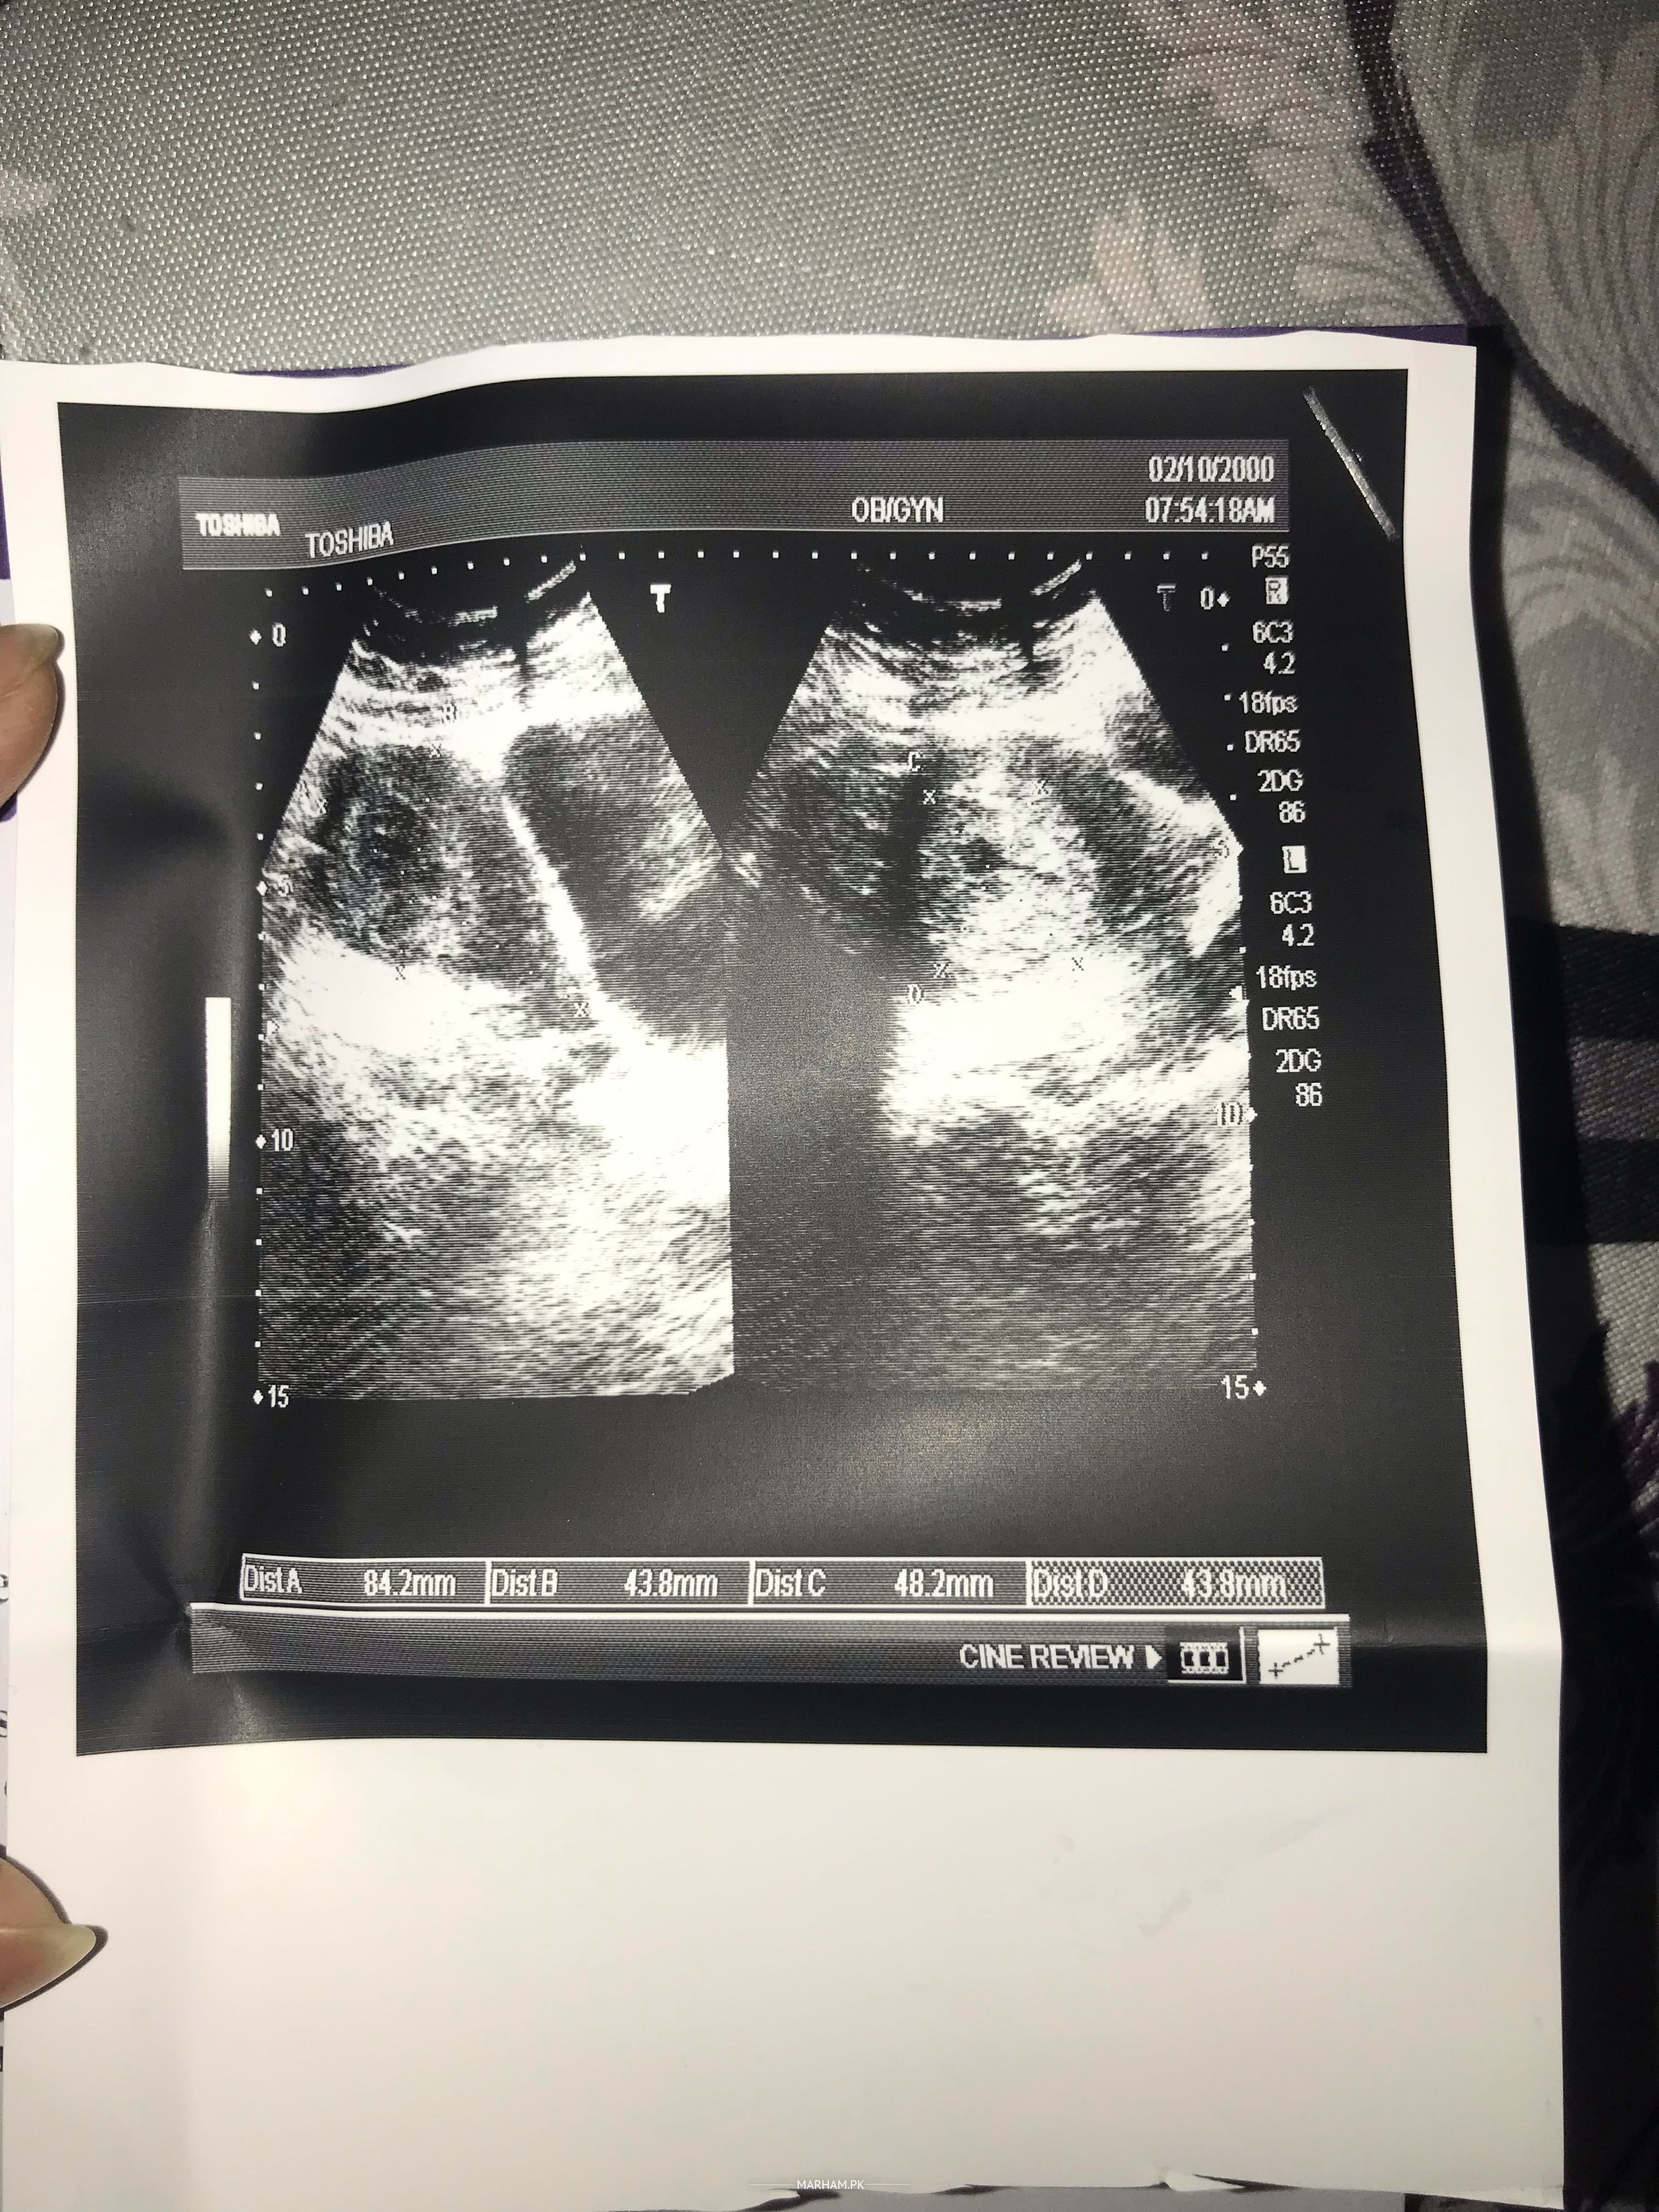

Assalam-o-Alaikum! I’m having blighted Ovum pregnancy and it’s been 12+ weeks. As i did my 1st scan i got to know about this and i consulted to different doctors and asked about this situation on Marham also every doc. suggested me to wait till 1st trimester gets completed and then repeat the scan if it would remain same then we’d go for termination. Now plz tell me that which medicines i need to start taking ‘cuz my body has already started bleeding 3 days ago and cramps are increasing day by day..I’m attaching the current scan also so u can understand the condition more clearly…